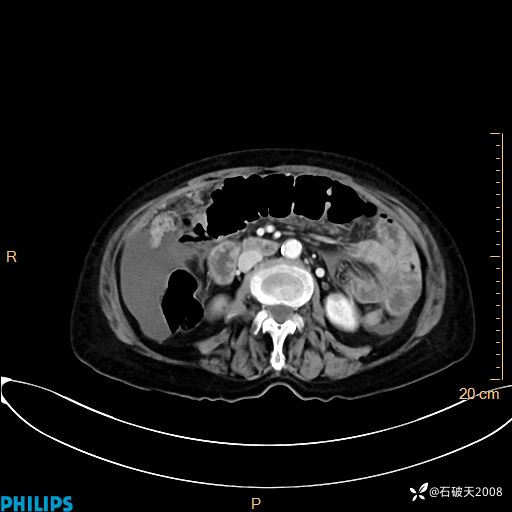

静脉期